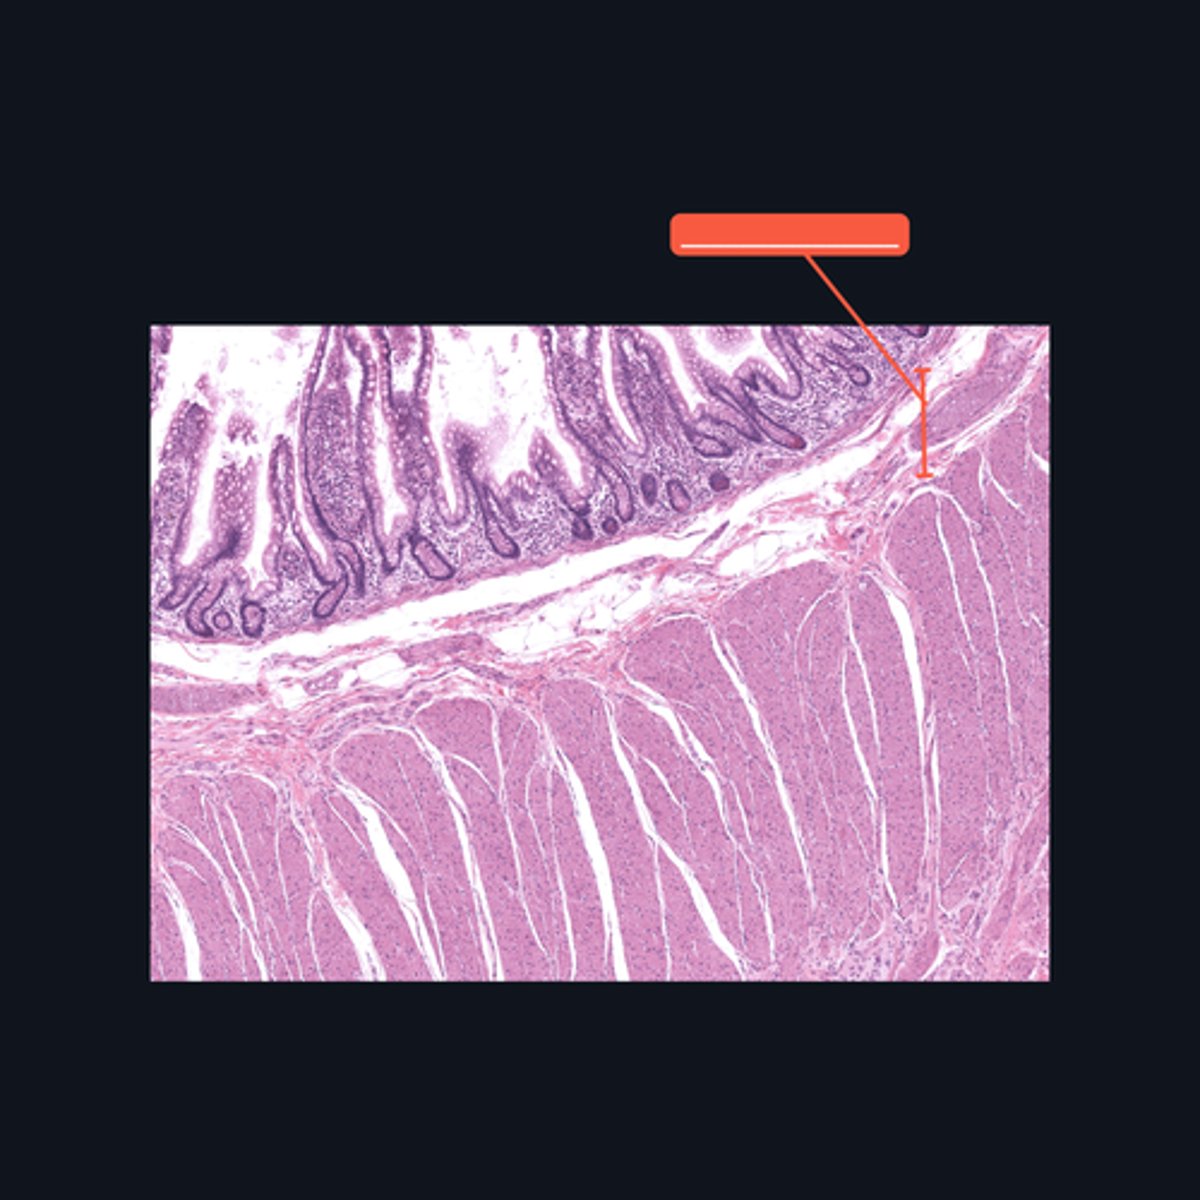

Muscularis Externa

Identify the pointed histologic layer of the digestive tract

Serosa

Identify the pointed histologic layer of the digestive tract